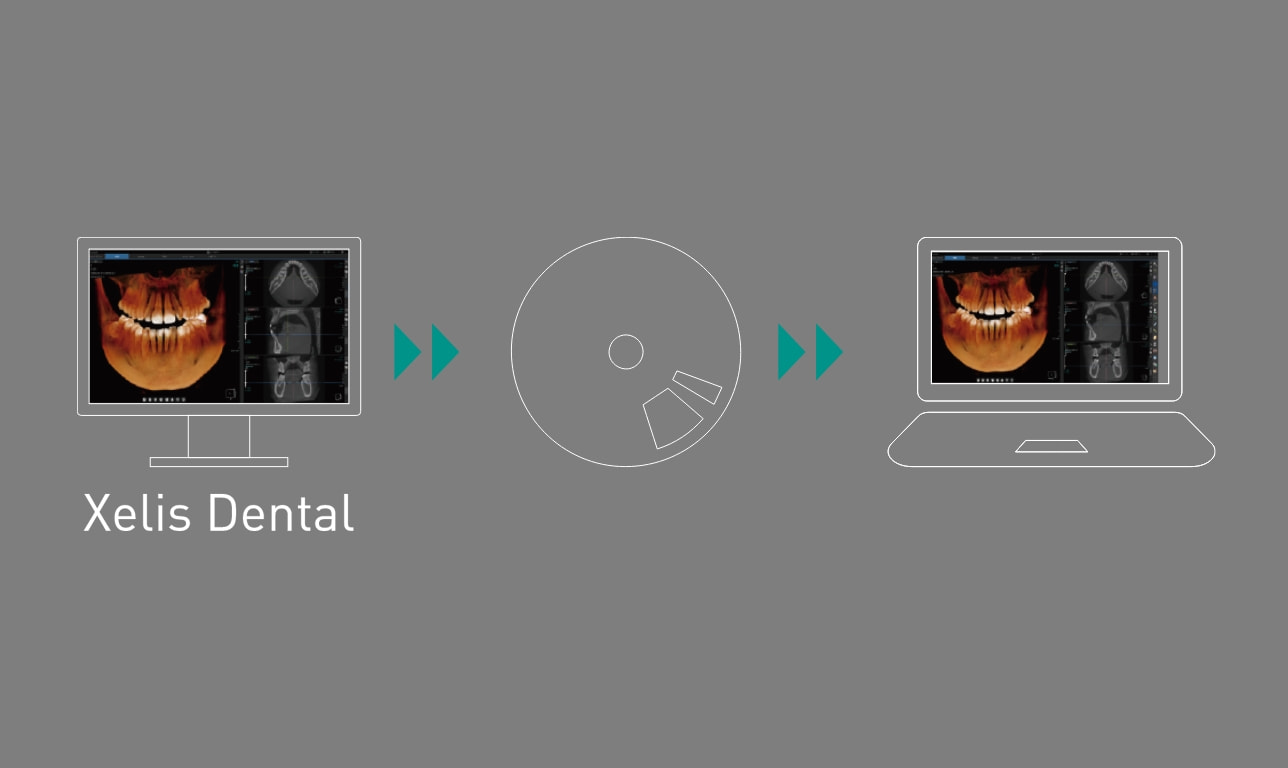

メディア出力(ビューアー付)

XelisDentalがインストールされていないPCでも、閲覧可能なビューアー付きのCT画像が出力可能です。